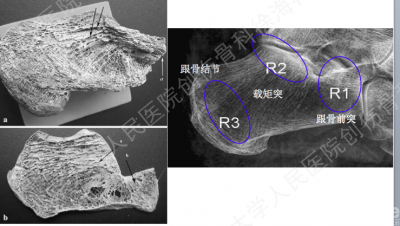

CT扫描图

困惑之处

你会像下图所示,选择外侧扩大入路的方式操作吗?